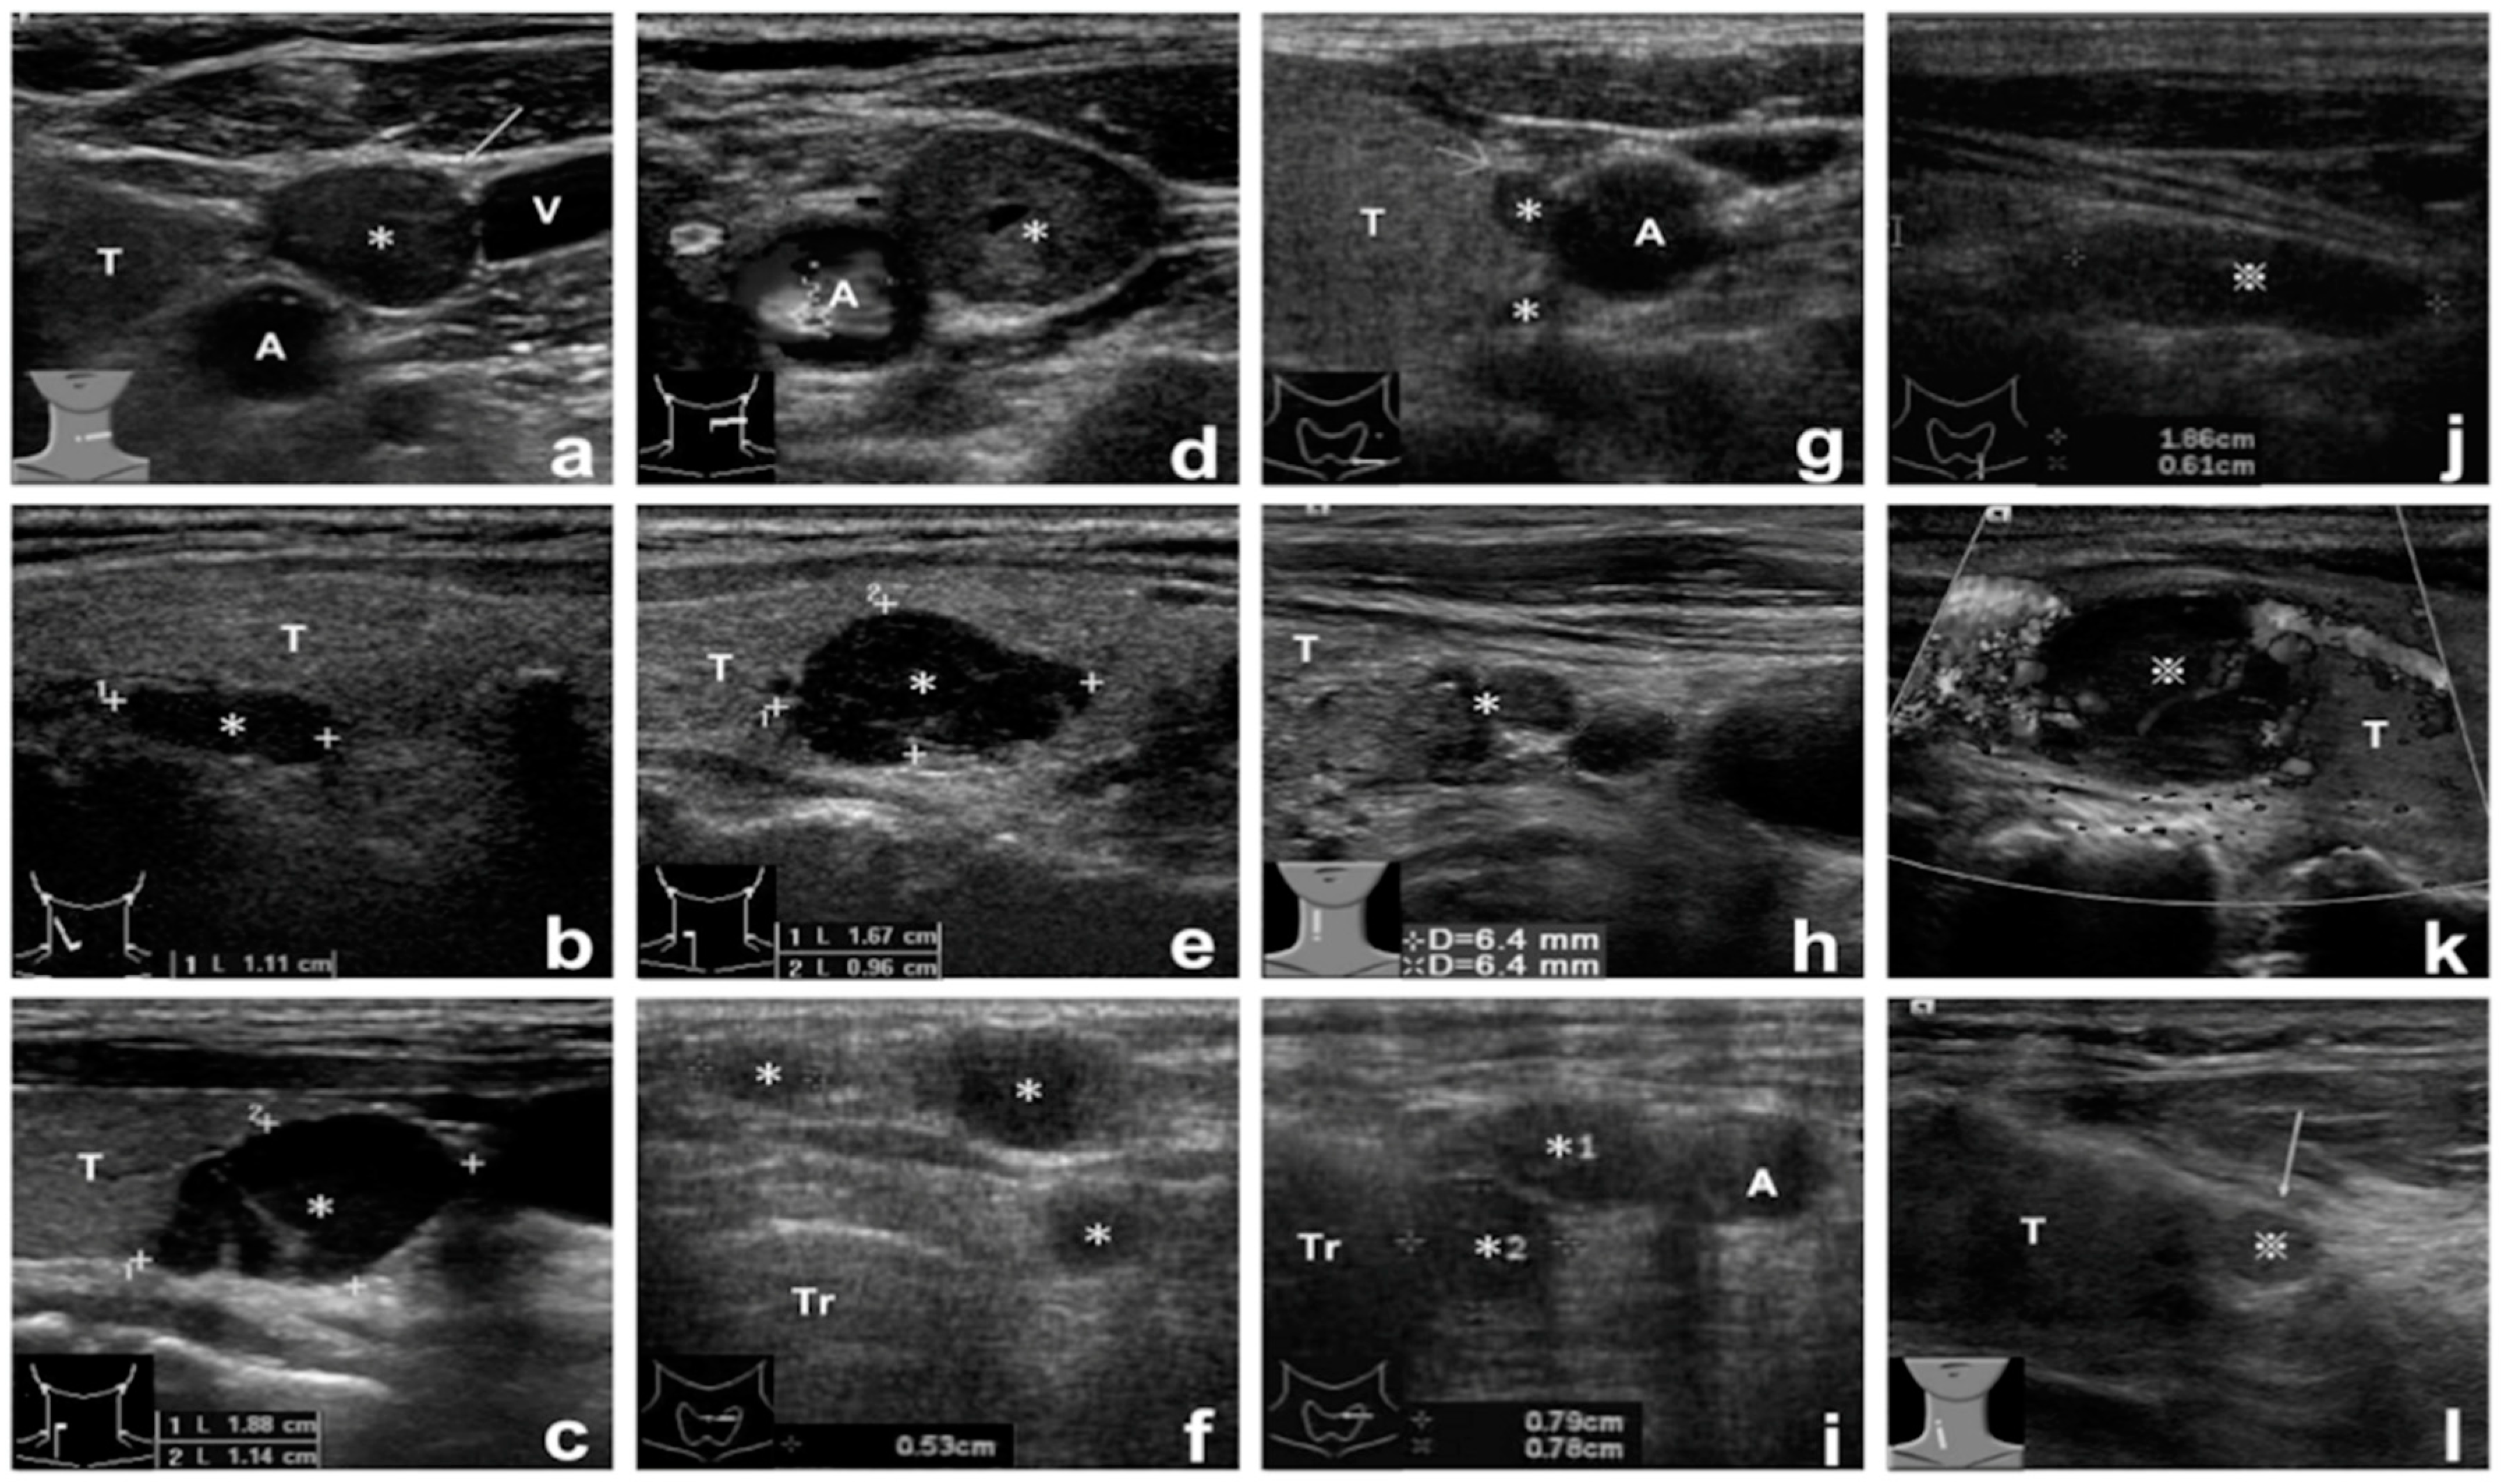

The patients received follow-ups until the end of June 2017. All data on demographics, localization, tissue aspirate PTH assay results, reoperative findings and procedures, pathological findings, and post-reoperative course were recorded and analyzed. The results of parathyroid sonography were classified as either suspicious or positive, and the results of parathyroid scintigraphy were classified as negative, suspicious, or positive. The suspicious parathyroid sonographic results were defined as neck lesions with unusual locations or atypical sonographic images including shape, size, and number (Figure 1). The results of parathyroid scintigraphy were determined with the agreement of both the surgeon and nuclear medicine specialist. The final diagnosis after reoperation was confirmed by the pathologists. The accuracy of the tissue aspirate PTH assays was calculated according to the reoperative results.

Figure 1.

Images of positive and suspicious parathyroid sonography lesions. (a–c) Case 1, 2, 6, with positive sonographic lesions. (d) Case 5, with suspicious left upper neck lesion. (e) Case 20, with suspicious intrathyroid lesion. (f) Case 24, with suspicious multiple subcutaneous lesions. (g) Case 25, with suspicious dumbbell shape lesion. (h) Case 8, with suspicious infrathyroid lobulated lesion. (i) Case 26-1, with suspicious multiple paratracheal lesions. (j) Case 14, with suspicious intrathymus lesion (false assay-negative). (k) Case 31, with suspicious intrathyroid lesion. (l) Case 26-2, with suspicious infrathyroid small lesion. ✻ Positive tissue aspirate PTH assay lesions. ※ Negative tissue aspirate PTH assay lesions. Demographic data of enrolled patients are listed in Table S1. Abbreviations: A, common carotid artery; V, internal jugular vein; T, thyroid; Tr, trachea.